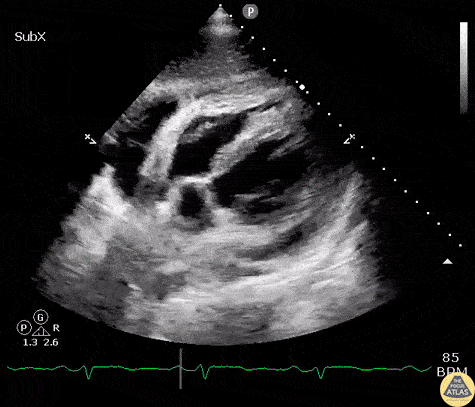

A young patient with a history of SLE presented to the ED with new onset HFpEF. A subcostal view revealed constrictive pericarditis with septal wall bouncing and a mild pericardial effusion. Image courtesy of Robert Jones DO, FACEP @RJonesSonoEM Director, Emergency Ultrasound; MetroHealth Medical Center; Professor, Case Western Reserve Medical School, Cleveland, OH View his original post here